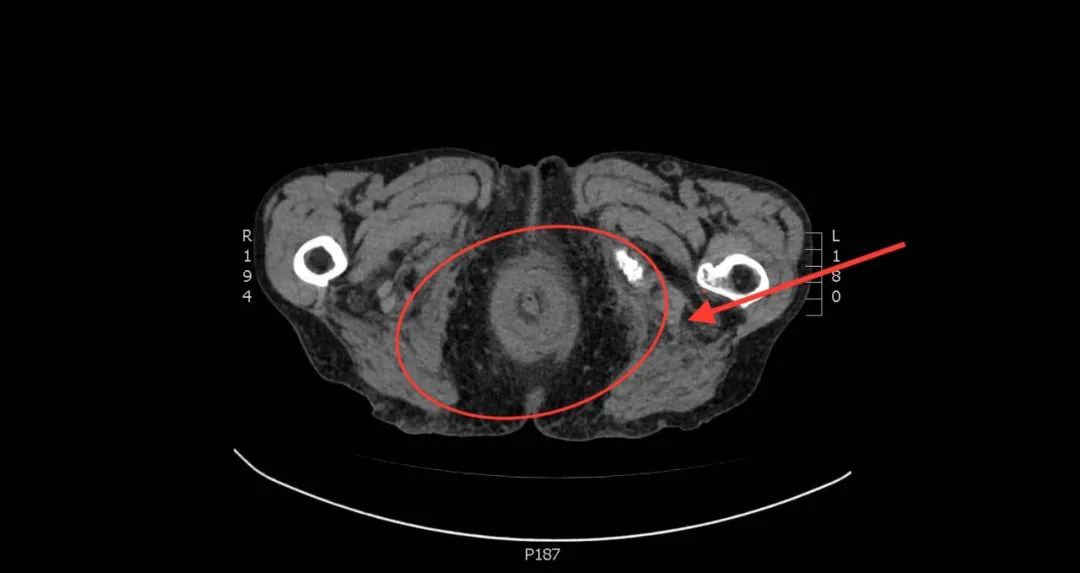

放射学诊断:

• 结肠造影后改变,直肠脱垂,直肠壁似环状增厚,周围水肿样改变。

术前影像